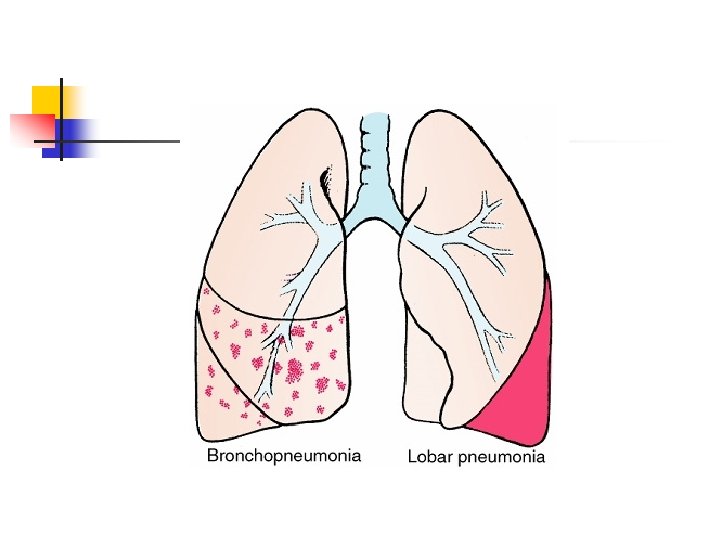

Pneumonia n Inflammation & infection of lunginfecting organisms typically inhaledorganisms transmitted to lower airways and alveoli causing inflammation- impairs gas exchange Etiology: bacteria, virus, Mycoplasma, fungus, or from aspiration or inhalation of chemicals or other toxic substances n Risk factors: cigarette smoking, chronic underlying disorders, severe acute illness, suppressed immune system, & immobility

Pneumonia Diagnostic: n Sputum and blood cultures, CBC, ABGs, CXR, & Bronchoscopy Nursing Diagnoses: n Ineffective airway clearance r/t thick, tenacious sputum n Ineffective breathing pattern r/t tachypnea, chest pain, & airway inflammation n Impaired gas exchange r/t exudate in alveoli n Activity intolerance r/t hypoxemia, fatigue n Acute pain r/t disease process n Imbalanced nutrition less than body required